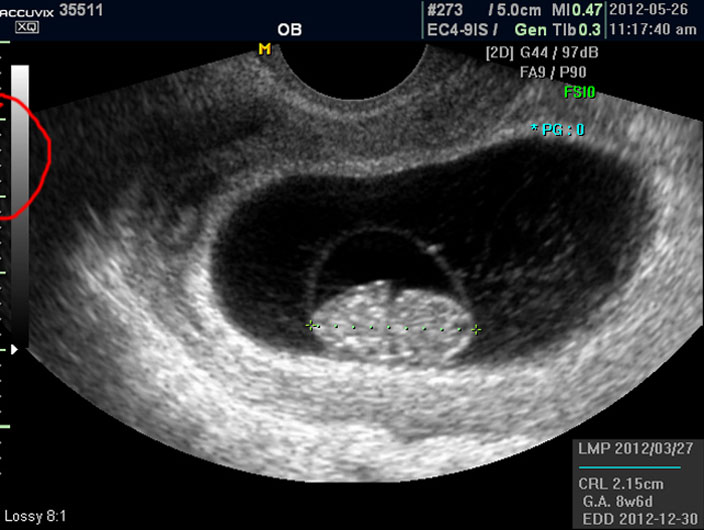

태아의 크기는 우측 하단에 실제 크기가 나와 있지만 아래 사진에서 빨갛게 표시한 부분의 안에 보이는 눈금이 1cm입니다.

이런 기준이나 지표들이 표시되는 것은 초음파 장비마다 조금씩 차이가 있고 위치도 다르지만 대개 비슷한 모양이라 한가지를 알면 다른 기종에서도 감상에 그리 어렵지는 않습니다.